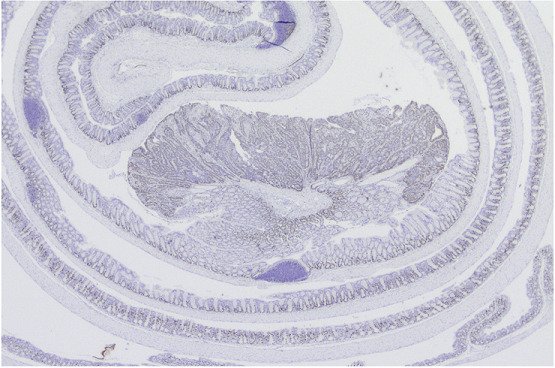

Uterine fibroids, also known as leiomyomas, are extremely common non-malignant tumours that arise from the smooth muscle layer of the uterus. Despite their benign nature, they can cause a variety of symptoms including excessive bleeding and abdominal pain, and negatively affect fertility and pregnancy. Their impact on women’s well-being is thus significant.

Work from our research group has revealed that there are at least four distinct subclasses of uterine fibroids, with characteristic genetic driver mutations. The subclasses show unique gene expression patterns and have been associated with distinct clinical and pathological characteristics.

In a recent study, based on fibroid patient samples collected in collaboration with clinicians at Danderyds Sjukhus and hospitals in Finland, we could for the first time demonstrate the clinical relevance of the fibroid subclasses. By retrospectively comparing tumour shrinkage in response to the volume-reducing drug ulipristal acetate (UPA), we found that treatment sensitivity was influenced by the molecular subclass. We are now further exploring how subclass specific features could potentially be used to predict treatment response and personalize treatment. To do this, we are setting up a tissue slice culture system in which thin sections of surgically removed uterine fibroids are cultured on membrane inserts. We are also evaluating the possibility of using liquid biopsies for pre-treatment subclassification.